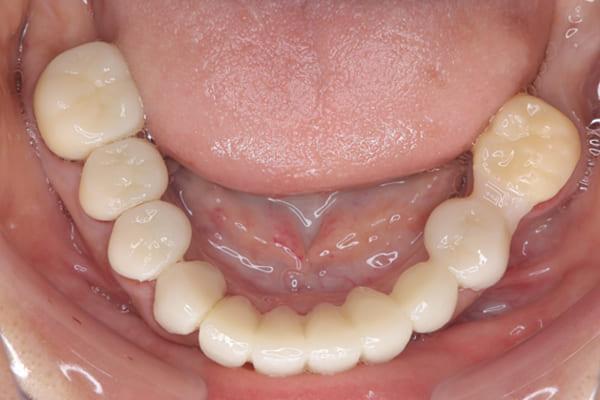

下顎治療後

治療前の入れ歯の奥歯は、治療後の義歯と比較しても分かるように、歯が削れ平らになった状態です。

これにより奥歯のかみ合わせは低くなり、前歯のみが強くあたり、かみ合わせにより上の前歯大きな負担がかかっていたことにより、上の前歯が折れたことが考えられます。